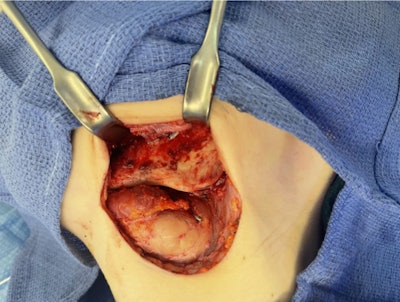

Intraoperative view through the left Risdon approach demonstrating cortical erosion and scleroses of the buccal plate of the left mandibular body, angle, and ramus prior to debridement.